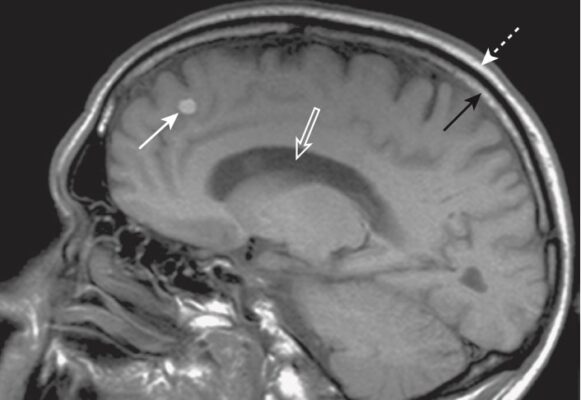

- Nếu dịch có màu tối, thì hình ảnh đang xem có thể là hình ảnh T1w (Hình 2, A).

- Nếu chất dịch sáng, thì hình ảnh đang xem có thể là hình ảnh T2w (xem Hình 2, B).

- Mỡ: mỡ dưới da và trong ổ bụng, mỡ trong tủy xương, các khối u chứa mỡ (xem Hình 2, A)

- Xuất huyết: thay đổi tùy theo thời gian của xuất huyết (Hình 3)

- Tuy nhiên, một nang đơn giản chứa nước sẽ tối trên ảnh T1w (và sáng trên ảnh T2w), vì hãy nhớ rằng ở T1 nước có màu tối (Hình 4)

- Melanin: ví dụ, u hắc tố (Hình 5)